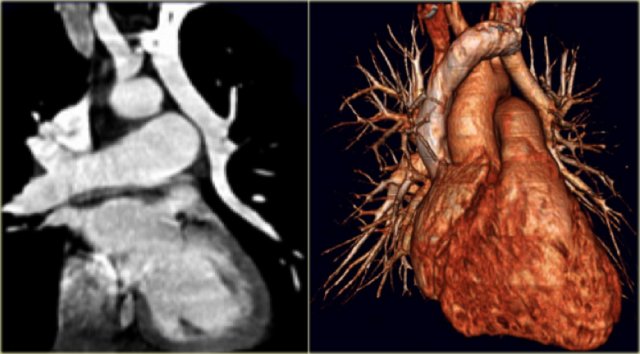

Patent Ductus Arteriosus Patent Ductus Arteriosus

Patent Ductus Arteriosus

On the left an adolescent with a murmur.

On axial image and reconstruction the patent ductus arteriosus is seen.

The ductus arteriosus is the communication between the pulmonary artery and the proximal descending aorta.

It shunts blood in utero from the right ventricle to the aorta to bypass the non-functioning lungs.

On the first day of life there is a functional closure and an anatomic closure with fibrosis in the first two weeks.

If it does not close these patients come to attention either with a murmur or later with pulmonary hypertension.

On the left a young adult with a murmur.

The cardiologists are not interested in the flow direction, but just want to confirm the diagnosis.

Notice the connection between the pulmonary artery and the descending aorta.

When the duct closes it may also calcify.

This a normal variant.